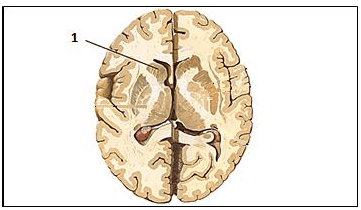

Saber a localização, bem como entender a função das estruturas encefálicas é fundamental para compreensão da circuitaria cerebral.

Assinale, a seguir, a nomenclatura da estrutura representada pelo número 1 na imagem.

Provas